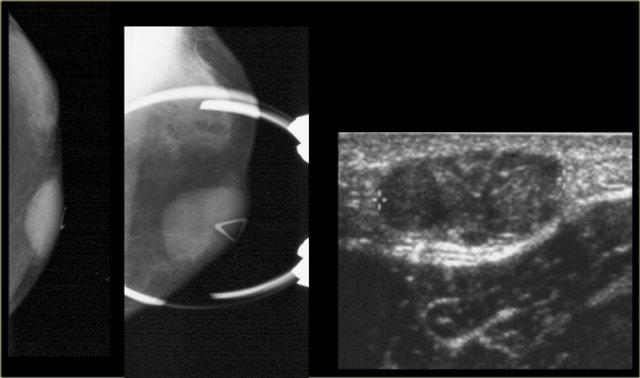

Bên trái là nhũ ảnh và hình siêu âm của một bệnh nhân có gynecomastia thể nốt tuyến.

Lưu ý tổn thương nằm ngay dưới núm vú.

Hình siêu âm cho thấy hình ảnh điển hình của gynecomastia: một khối giảm âm với bờ thùy múi hoặc thậm chí có gai.

Nếu đây là hình ảnh của một phụ nữ, bạn sẽ nhận định đây là một khối có vi thùy múi và gai, tức là Birads IV hoặc V.

Ở nam giới, đây là hình ảnh điển hình của gynecomastia.

Bên trái là cùng hình siêu âm đó, nhưng ở tư thế bình thường.

Lưu ý hình ảnh trông ‘ác tính’ như thế nào.